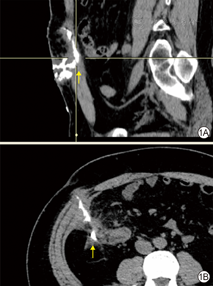

造影检查由具备相关经验的放射科医师完成。将对比剂(碘剂或钆剂)灌注入窦道(腔)创面,保持合适的体位和保证充分的灌注时间,使对比剂充分流布和灌注至窦道(腔)创面内,再行CT和/或磁共振成像检查。造影检查完成后由放射科医师行三维重建以呈现窦道(腔)创面的三维全貌[7]。对于邻近体腔的窦道(腔)创面,创面修复科医师结合影像学结果、窦道(腔)创面探查情况和病史,综合研判该创面是否与体腔相通,如是则需请其他相关科室医师会诊。见图1。

注:箭头示造影剂